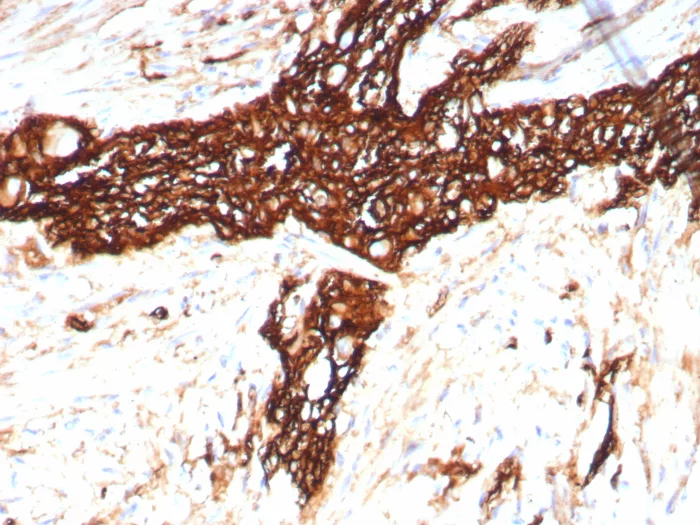

Formalin-fixed, paraffin-embedded human colon stained with CD56 Recombinant Mouse Monoclonal Antibody (rNCAM1/8758). HIER: Tris/EDTA, pH9.0, 45min. 2°C: HRP-polymer, 30min. DAB, 5min.

This MAb reacts with an extracellular domain (close to transmembrane) of CD56/NCAM. Three isoforms of neural cell adhesion molecule (NCAM) are produced by differential splicing of the RNA transcript from a single gene. The 135kDa isoform is the basic molecule, which is glycosylated or sialylated to produce the mature species. Anti-CD56 recognizes two proteins of the neural cell adhesion molecule, the basic molecule expressed on most neuroectodermally derived tissues and neoplasms (e.g. retinoblastoma, medulloblastomas, astrocytomas, neuroblastomas, and small cell carcinomas). It is also expressed on some mesodermally derived tumors (rhabdomyosarcoma). Anti-CD56 plays an important role in the diagnosis of nodal and nasal NK/T-cell lymphomas.